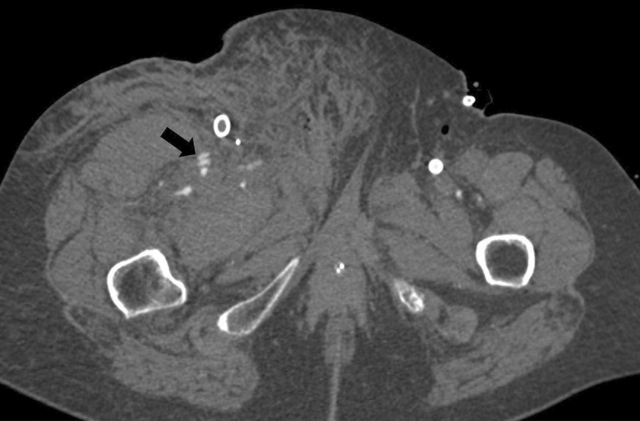

Figure 2

An axial CT showing extensive inguinal blood at the level of the right superficial femoral artery.